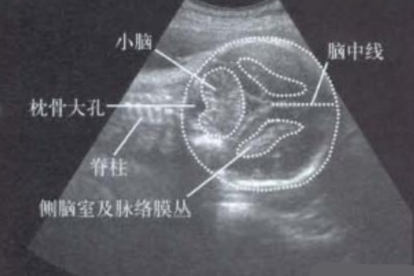

后颅窝肿瘤如髓母细胞瘤或听神经瘤逐渐增大,直接挤压小脑组织并向枕骨大孔方向移位。患者可能出现步态不稳、眼球震颤及持续性头痛。诊断依赖MRI增强扫描,治疗需手术切除肿瘤,术后可辅以注射用替莫唑胺等化疗药物。

高血压或脑血管畸形引发小脑部位出血,血肿占位效应迫使小脑扁桃体下疝。典型表现为突发眩晕、共济失调及瞳孔不等大。急诊处理包括静脉滴注乌拉地尔注射液控制血压,严重者需行脑室穿刺引流术。

脑脊液循环通路受阻导致脑室扩张,第四脑室压力传导至小脑。常见于先天性导水管狭窄或蛛网膜下腔出血后,可见头围增大、视乳头水肿。治疗采用脑室-腹腔分流术,术后需定期复查头颅CT评估分流管功能。